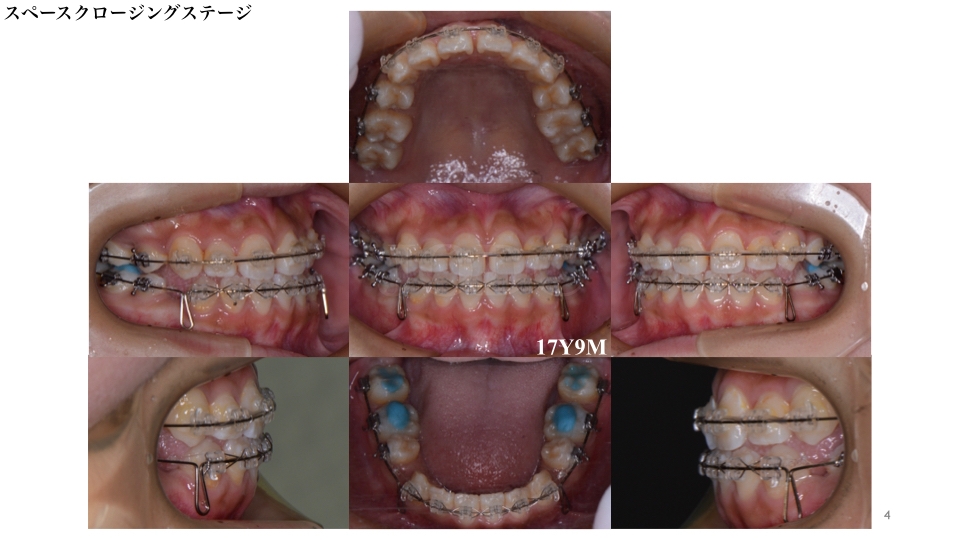

スペースクロージングステージです。

ワイヤーを用い、ご自身でかけていただくゴム(顎間ゴム)と併用し抜歯後のスペースの閉鎖を行いました。